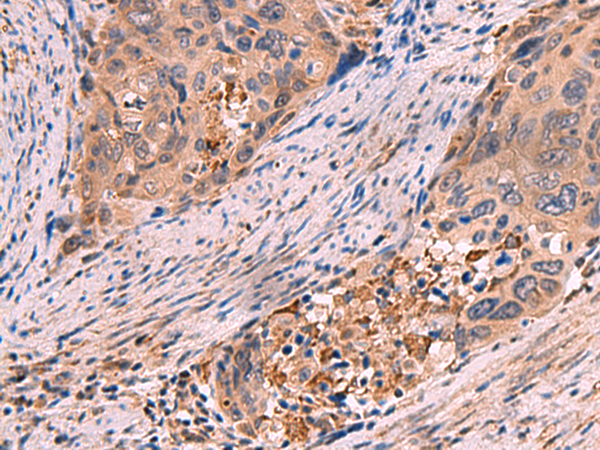

分类: 科研抗体货号: P10203别名: RaLP; SHCD应用: IHC反应种属: Human